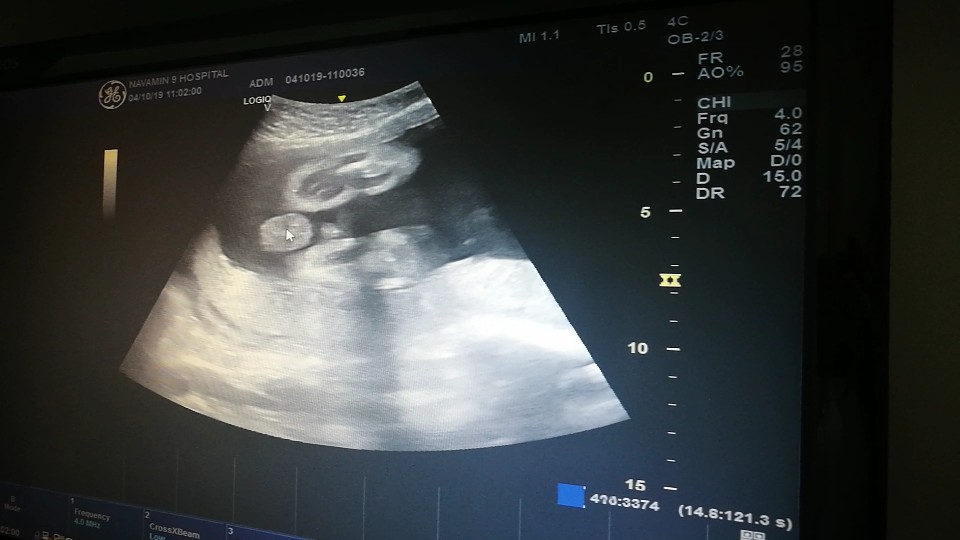

คุณลุงหมอบอกมีกลีบ?ใครมีกลีบ ใครมีแท่ง ลงมาอวดกันจร้า

อ้าขาเลย ผู้หญิงค่ะ

จู๋เด่นมาเลยค่ะแม่

แท่งจ้ะ โด่เด่มาก😂

กระจู๋ผมใหญ่คับ😂😂

เจ้าหำน้อยของแม่ 🤗

โด่ชัดเจนมากคร้า555